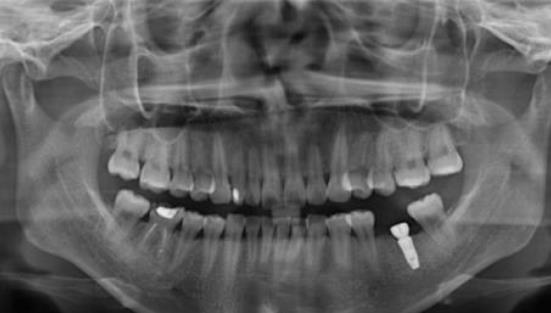

崔南醫(yī)生種植牙案例效果展示:

聽(tīng)說(shuō)重慶種植牙技術(shù)比較好,爸爸的牙齒少了很多,如果不及時(shí)的去補(bǔ)種就會(huì)影響到周?chē)难例X,假牙也不方便,所以決定去重慶口腔醫(yī)院種植牙齒,聽(tīng)說(shuō)種植牙齒跟真牙一樣,隨便用,不會(huì)對(duì)生活造成影響,經(jīng)過(guò)仔細(xì)了解重慶種植牙的價(jià)格后,決定帶爸爸去重慶牙衛(wèi)士口腔醫(yī)院看看。

種植牙前:

經(jīng)過(guò)多方面的對(duì)比之后決定帶爸爸去重慶牙衛(wèi)士口腔醫(yī)院種植牙,來(lái)到醫(yī)院后,醫(yī)生仔細(xì)地檢查了爸爸的身體,經(jīng)過(guò)仔細(xì)的確認(rèn)爸爸的身體沒(méi)有任何異常,醫(yī)生才選擇了手術(shù),手術(shù)前爸爸有些緊張,但醫(yī)生耐心的溝通,徹底消除了爸爸的緊張,開(kāi)始準(zhǔn)備手術(shù),差不多花了3個(gè)多小時(shí),手術(shù)結(jié)束了。

種植牙中:

父親說(shuō),這次手術(shù)并沒(méi)有疼痛感,整個(gè)手術(shù)都很輕松,牙齒種植后也會(huì)有些不適應(yīng),可能是麻藥的緣故,醫(yī)生說(shuō)麻藥藥效散去后會(huì)有一些疼痛感出現(xiàn),爸爸說(shuō)是有一些疼痛感出現(xiàn),但不是很明顯,這種疼痛也可能是麻藥的緣故。

種植牙術(shù)后半年:

牙齒種植距今已有半年左右,爸爸說(shuō)已經(jīng)適應(yīng)了這個(gè)情況,一切都很好,牙齒也可以咬上各種各樣的東西,現(xiàn)在爸爸再也不會(huì)擔(dān)心這種食物不能吃,那種食物不能吃,所有的東西都可以吃,硬的、酸的、甜的食物都不會(huì)造成牙痛,這回種牙齒真的很滿(mǎn)意。